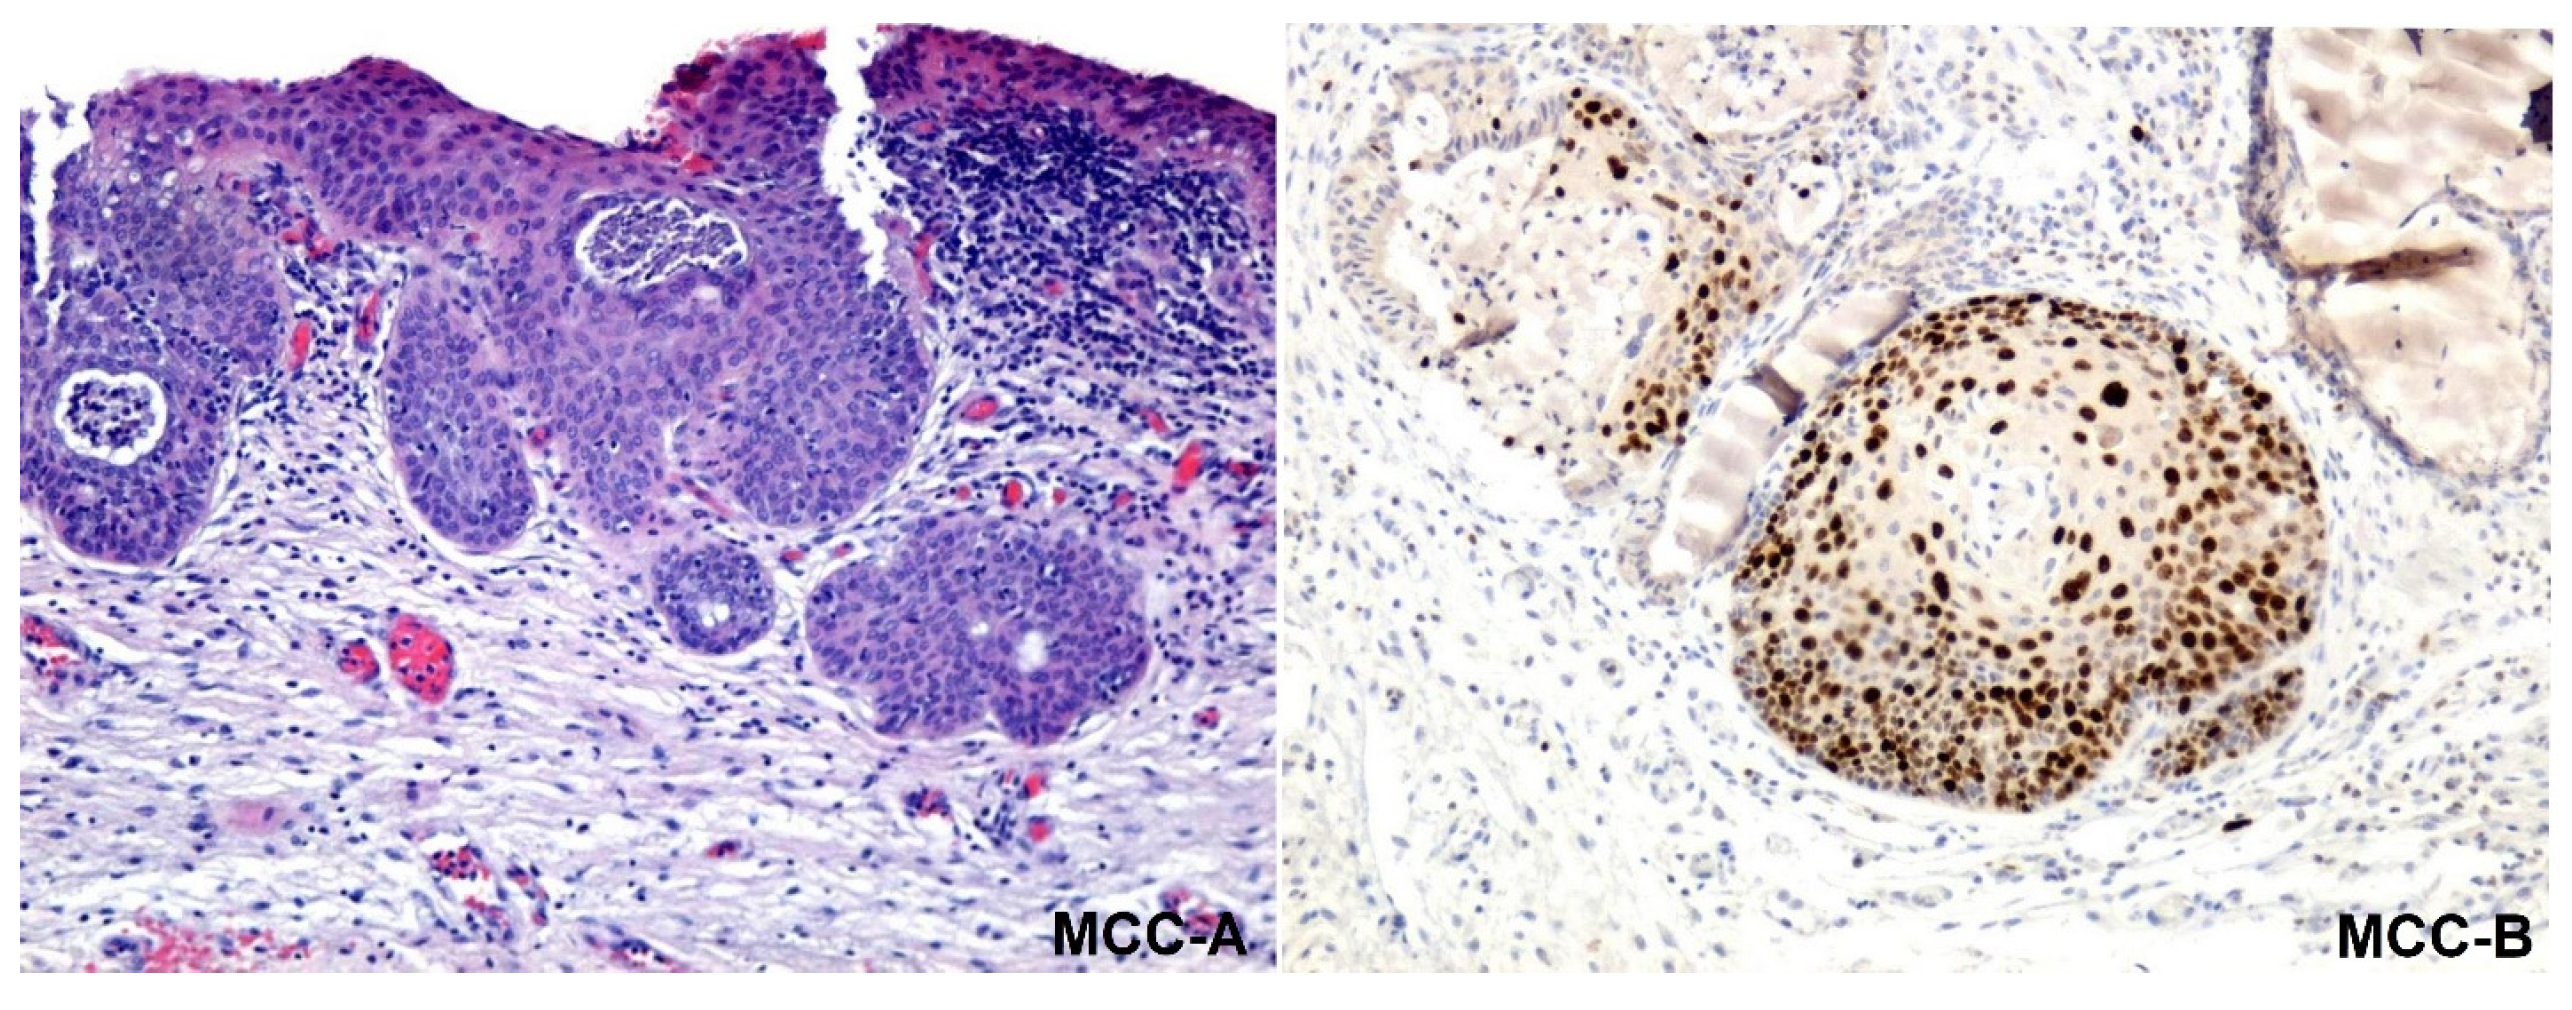

| Anti-Ki67 1 |

| Dako |

| MIB-1 |

| Ethylenediaminetetraacetic acid (EDTA), pH9 |

| Monoclonal mouse anti-human Ki67 |

| 1:50 |

| Cells in the division in G1, S, G2 and M phase |